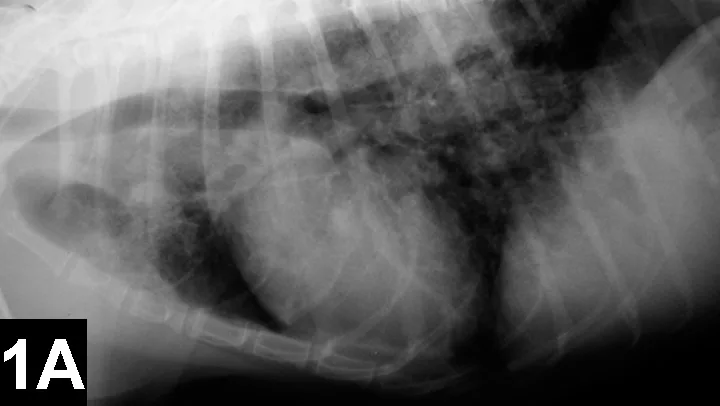

FIGURE 1

Lateral (A) and VD (B) views of a patient with heartworm disease and PTE. Note blunting and enlargement of the pulmonary arteries and the heavy interstitial to alveolar infiltrate.

• In patients with PTE caused by heartworms, thoracic radiography may show signs of blunting and enlarged pulmonary arteries, plus interstitial to alveolar infiltrate (Figure 1).

• In patients with PTE secondary to other underlying disease, radiographs may appear normal.

• Additional findings may include:

• Right-sided heart changes from D immitis infection or pulmonary hypertension

• Areas of lucency and decreased perfusion caused by reduction of pulmonary blood volume

• Pleural effusion

• Interstitial or alveolar infiltrate